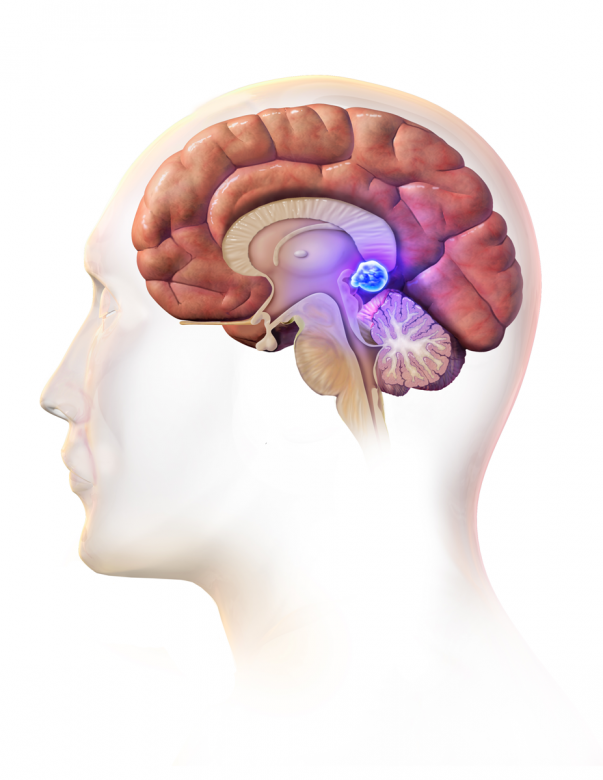

Brain cancer

“Brain and spinal cord (also known as central nervous system, or CNS) tumors can be benign or malignant.”

Image Credit: BruceBlaus / Wikimedia Commons.